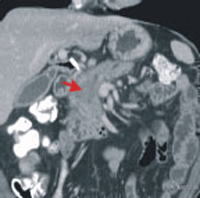

(1)實質性腫瘤:以胰腺癌最為常見,約佔胰臟所有惡性腫瘤的85%,因此一般所俗稱的胰臟癌即是指胰腺癌(如左圖,箭頭處為胰臟癌)。至於其餘如由內分泌細胞而來的胰臟內分泌腫瘤、胰腺泡瘤、實體偽乳頭瘤、淋巴瘤等均十分罕見。另外,胰臟有時也會發生從其他器官的癌症轉移而來的腫瘤。